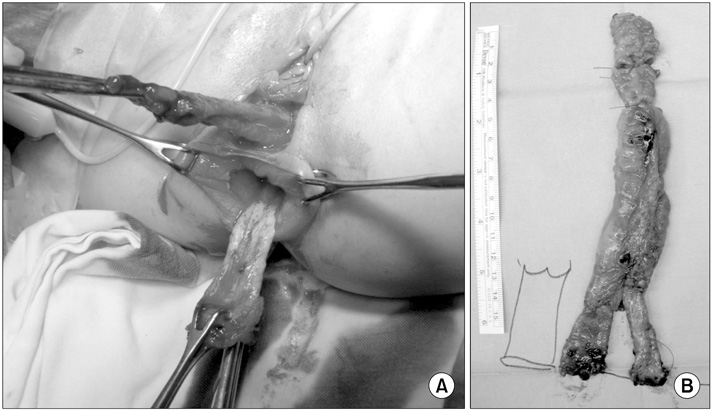

Fig. 2). A catheter was inserted through the ectopic anus, and an intraoperative contrast study and sigmoidoscopy were performed. A parallel tubular duplication with a common wall was found. The common wall extended 5 cm from the anal verge to the sigmoid colon and then 20 cm to the level of the proximal sigmoid colon. Proximally, the anterior duplication and normal colon merged and formed a normal colon. Because most of the stool moved through the anterior duplication and because the diameter of the anterior duplication was larger than that of the normally located colon (

Fig. 3), complete resection of both the anterior duplicated bowel and posterior native bowel up to the merging point with colo-anal anastomosis was performed (

Fig. 4).

Fig. 5 shows a schematic diagram of surgical findings. Pathologic examination confirmed a duplicated colonic segment with a common proper muscle layer. The patient was discharged on the 8th postoperative day without incident. During a 3-year follow-up, she defecated normally without complications.

Fig. 3Intraoperative findings. (A) The intraoperative contrast study revealed that the contrast injected via the anterior anorectal duplication filled the normal colon and rectum and that there was a connection between the duplication and the normal colon at the level of the proximal sigmoid colon. (B) Intraoperative sigmoidoscopy at the merging point revealed that a catheter inserted via the anterior anorectal duplication could be observed by a scope inserted via the normal anus.

Fig. 4Operative findings. (A) The tubular anorectocolonic duplication and the normal anorectum were dissected from neighboring structures. (B) Resected specimen.